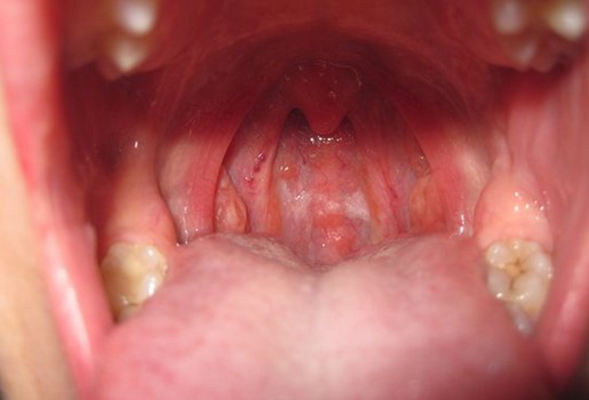

扁桃體週膿腫圖片